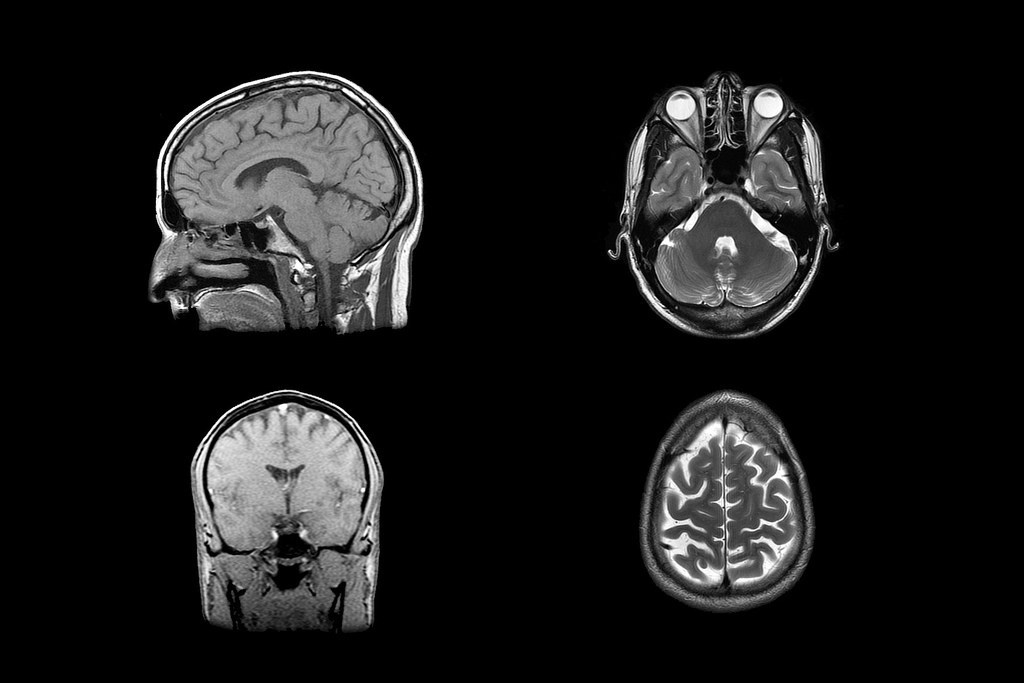

연구진은 40명의 실험 참가자들에게 서로 다른 두 가지 통증을 느끼게 한 후, fMRI(기능성 자기공명영상장치)를 통해 사람들의 뇌가 어떻게 반응하는지 관찰했습니다.

먼저 팔에 뜨거운 열이 가해졌을 때 뇌에서 신체적 통증을 느끼는 부분이 활성화됐어요. 지극히 자연스러운 결과죠. 놀라운 것은 참가자에게 이별의 순간을 떠올리게 했을 때도 신체적 통증을 느끼는 부분이 활성화됐다는 점이에요.